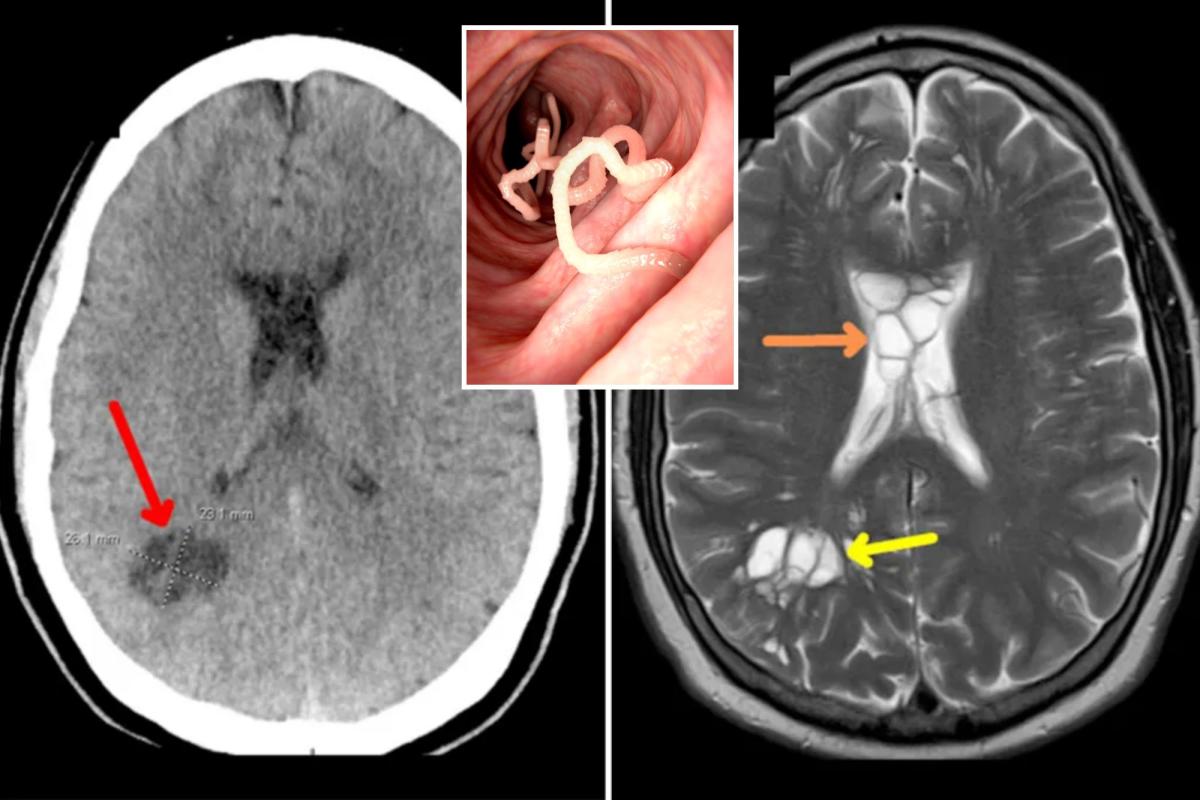

في هذه الحالة، بالإضافة إلى التورم، أصيب المريض بكيسات على جانبي دماغه. تم تحديد هذا لاحقًا على أنه الدودة الشريطية التي وضعت بيضها داخل دماغ الرجل.

كان رجل من فلوريدا يبلغ من العمر 52 عامًا يعتقد أنه يعاني من الصداع النصفي الشديد، وكان يعاني في الواقع من غزو غريب للدودة الشريطية في دماغه، بسبب تناول لحم الخنزير المقدد غير المطبوخ جيدًا.

أدت حالة العاصفة المثالية إلى حالة من داء الكيسات المذنب العصبي – وهو المصطلح العلمي لطفيلي يضع بيضًا يصيب مناطق عديدة من الجسم.